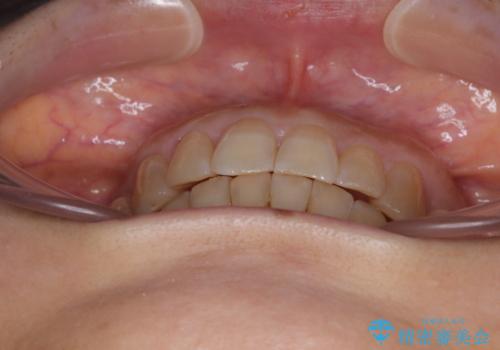

ディープバイトと前歯のデコボコ インビザラインによる矯正治療

- 前歯のディープバイトと叢生を気にして来院された患者様です。

目立ちにくい装置を希望されていたため、ワイヤー装置とインビザラインを提案したところ、インビザラインを希望されました。

下顎大臼歯が手前に倒れていたため、起き上がらせることで咬み合わせ高さを挙上し、ディープバイトと叢生を改善することとしました。